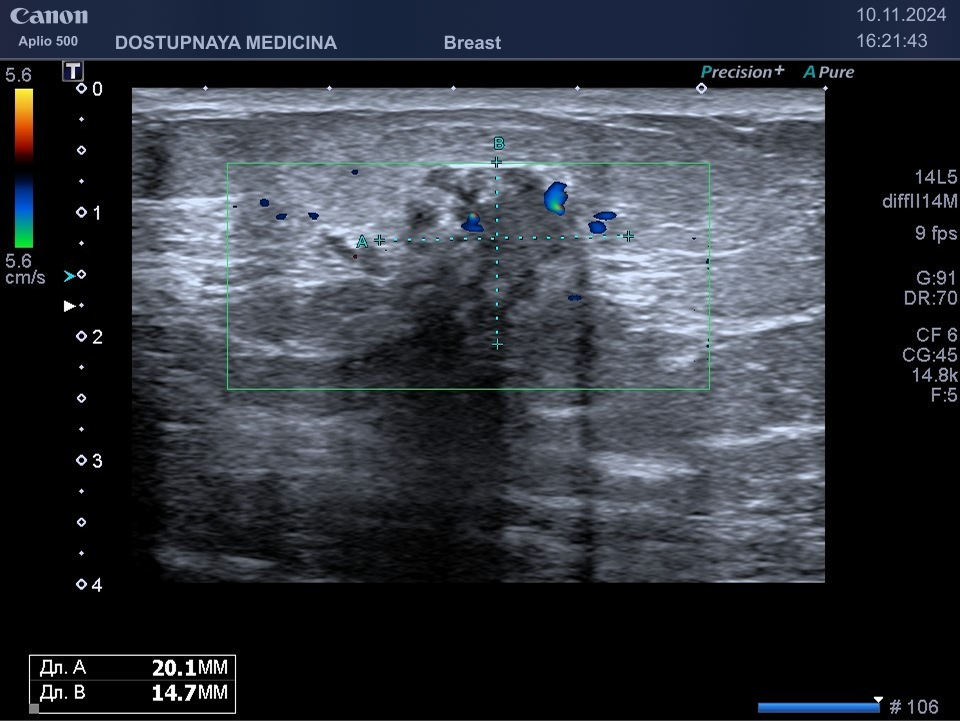

При ультразвуковом исследовании в кисте может быть визуализирован папиллярный компонент с кровотоком в режиме ЦДК. Так могут выглядеть цистаденопапилломы, которые считаются аблигатным предраком.